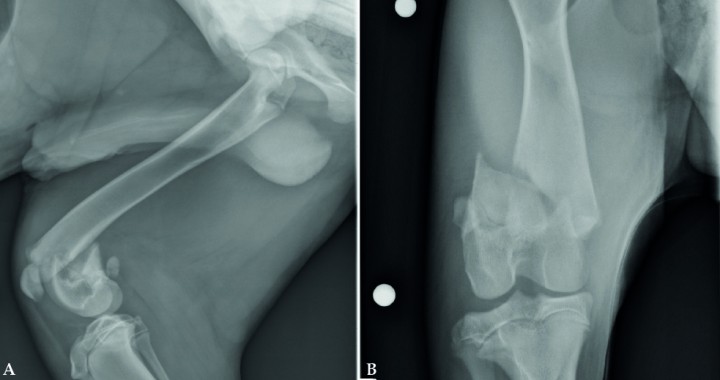

<p>Imágenes radiográficas de un cachorro de 6 meses con una fractura de la tuberosidad tibial (TT). Véase el desplazamiento proximal de la tuberosidad tibial (Fig. 3A) como consecuencia de la tracción del ligamento rotuliano. Es muy importante evaluar la proyección craneocaudal (Fig. 3B) para un completo estudio radiológico. Si se compara con el miembro derecho se podría apreciar una localización de la tuberosidad tibial más proximal, así como un desplazamiento proximal de la rótula. Su tratamiento es generalmente quirúrgico con la estabilización de la TT con agujas de Kirschner y un cerclaje (banda de tensión). En animales muy jóvenes puede ser necesaria la retirada de los implantes para evitar un cierre fisario prematuro y desplazamiento distal de la TT.</p>

Imágenes radiográficas de un cachorro de 6 meses con una fractura de la tuberosidad tibial (TT). Véase el desplazamiento proximal de la tuberosidad tibial (Fig. 3A) como consecuencia de la tracción del ligamento rotuliano. Es muy importante evaluar la proyección craneocaudal (Fig. 3B) para un completo estudio radiológico. Si se compara con el miembro derecho se podría apreciar una localización de la tuberosidad tibial más proximal, así como un desplazamiento proximal de la rótula. Su tratamiento es generalmente quirúrgico con la estabilización de la TT con agujas de Kirschner y un cerclaje (banda de tensión). En animales muy jóvenes puede ser necesaria la retirada de los implantes para evitar un cierre fisario prematuro y desplazamiento distal de la TT.